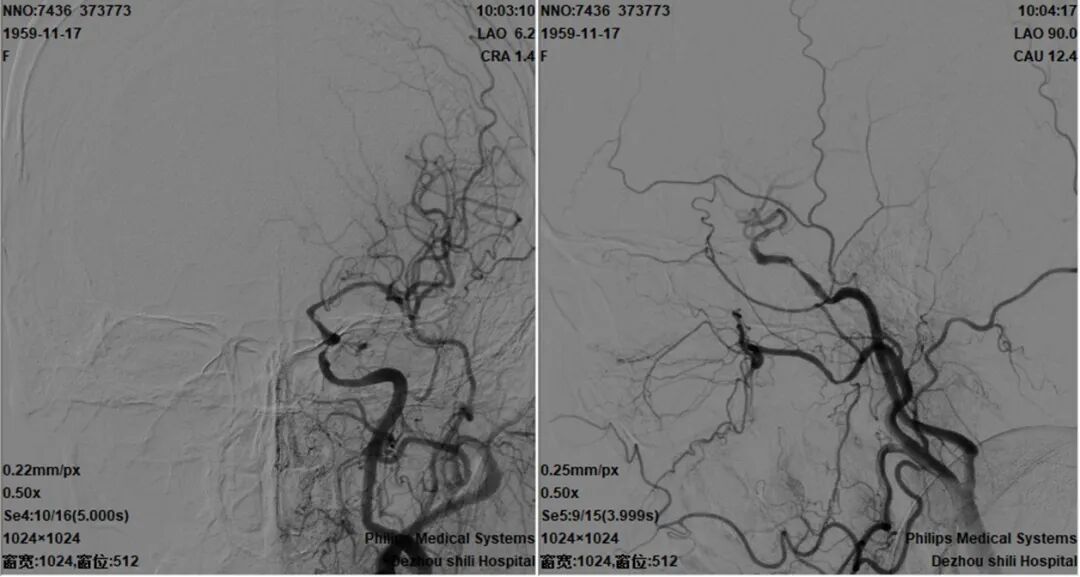

治疗中影像

导引导管到位,导丝通过病变,球囊通过病变。

球囊扩张过程。

扩张后造影。

支架通过病变。

支架释放。

术后造影。